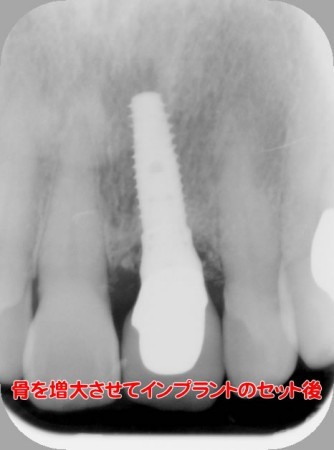

前歯のインプラント Kさん